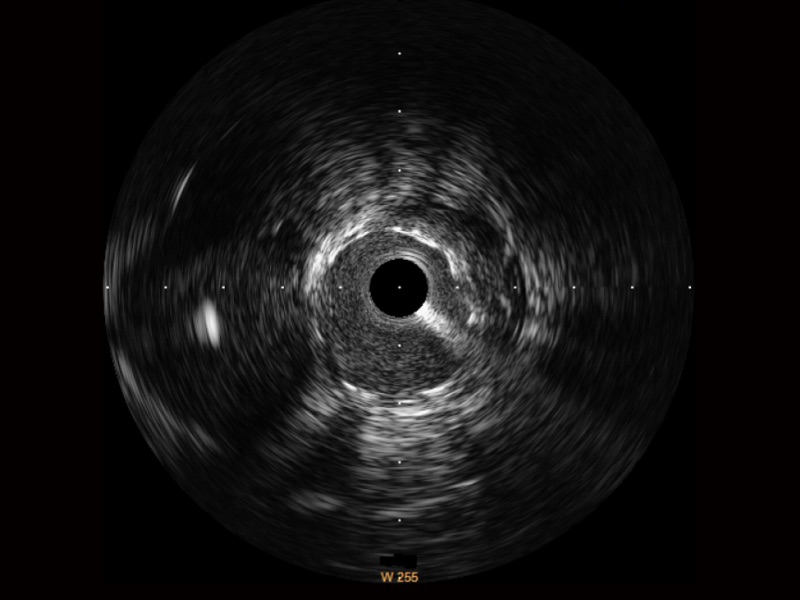

玖鼎集团宽频IVUS图像

对比传统IVUS导管成像,玖鼎集团宽频IVUS图像的近场支架梁显影更细腻,远场中膜外血管仍清晰可辨,兼顾远中近,兼顾分辨力与穿透深度